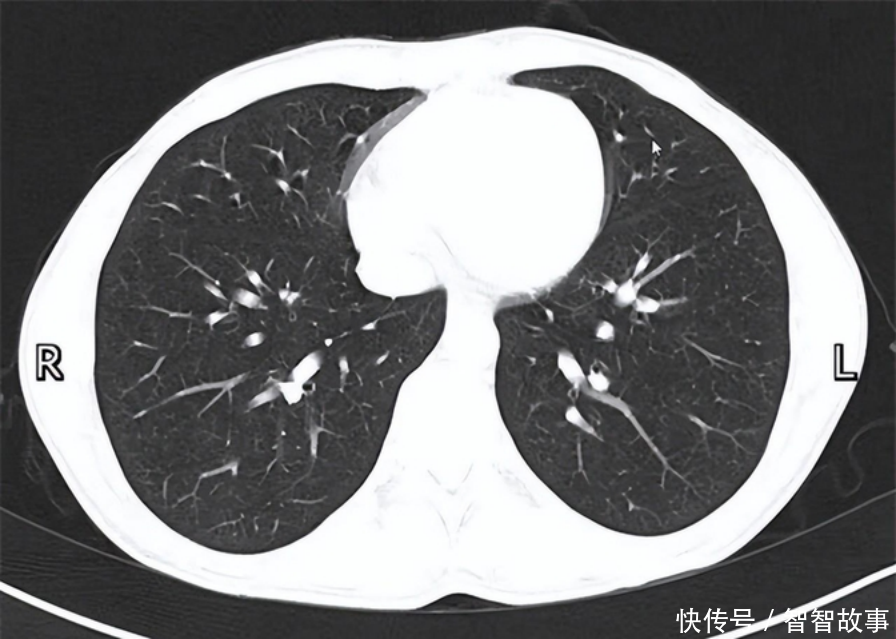

男子不痛不痒,却查出肺癌晚期?医生提醒:5大症状,莫忽视